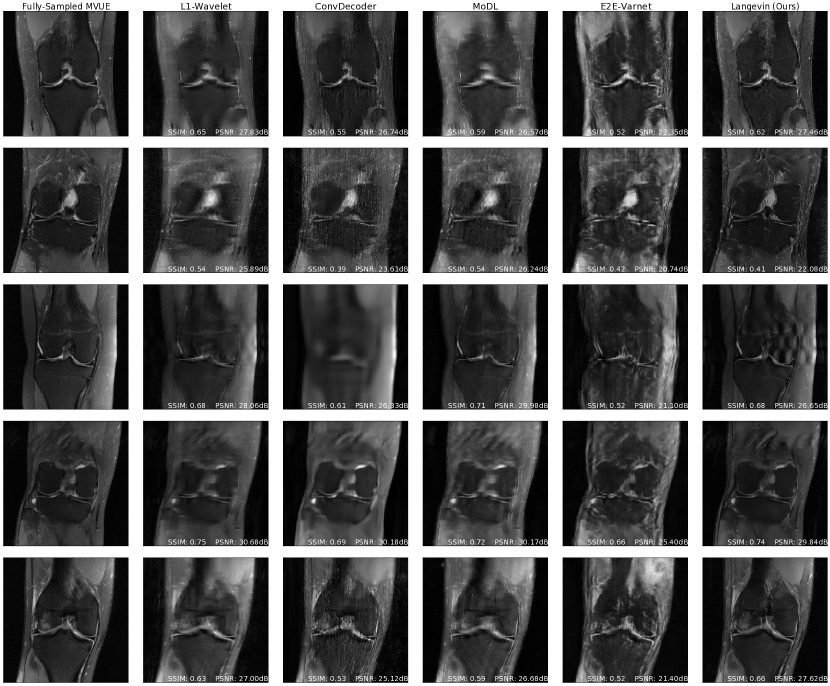

Refer to caption

Figure 3: Comparative reconstructions of a 2D abdominal scan with uniform random under-sampling in the horizontal direction at R=4𝑅4R=4. None of the methods were trained to reconstruct abdomen MRI. Our method uses a score-based generative model trained on brain images (as explained) and obtains good reconstructions. The red arrows indicate missing details or artifacts in the kidney structure.

We first highlight that an advantage of the proposed approach is the invariance to the sampling scheme during training. In contrast, this is a design choice that must be made for supervised end-to-end methods, which here were trained on equispaced, vertical sampling masks, following the fastMRI 2020 challenge guidelines [94, 66]. As our results show, this affords us a significant degree of robustness across a wide distribution of sampling masks during inference.

We now consider the more difficult problem of reconstructing different anatomies than the ones seen during. This was previously investigated in [19], which concluded that all methods suffer a drastic shift due to the various changes in scan parameters between body parts. In contrast to prior work, our main finding is that the proposed score-based model retains a significant degree of robustness under these shifts, and outputs excellent qualitative reconstructions. In some cases, some end-to-end methods retain robustness as well.

Figures 2c & 5c show PSNR and SSIM scores obtained on reconstructed abdominal scans obtained from [1] at different acceleration factors. This represents both an anatomy and sampling pattern shift, and it can be seen that our method, MoDL, and the 1subscript1\ell_{1}-Wavelet algorithm retain their competitive advantage, while the ConvDecoder and E2E-VarNet suffer severe performance losses. Figure 3 further shows a qualitative comparison of a reconstructed abdominal scan at R=4𝑅4R=4, with highlighted artifacts. Appendix E shows another abdomen scan.

Finally, Figures 2d & 5d show PSNR and SSIM scores obtained on fastMRI knee reconstructions, while Figure 1 (bottom row) shows the accompanying qualitative plots. This anatomy is challenging especially because of the poor signal-to-noise ratio conditions, which can be seen even in the ground-truth image. It can be noticed that this is the most severe shift for all methods, but our approach still shows the best performance at R=2,4𝑅24R={2,4} and a significantly lower variance. Appendix D shows more examples of knee reconstructions with and without fat suppression, and Figure 20 shows metrics on fat suppressed knees.